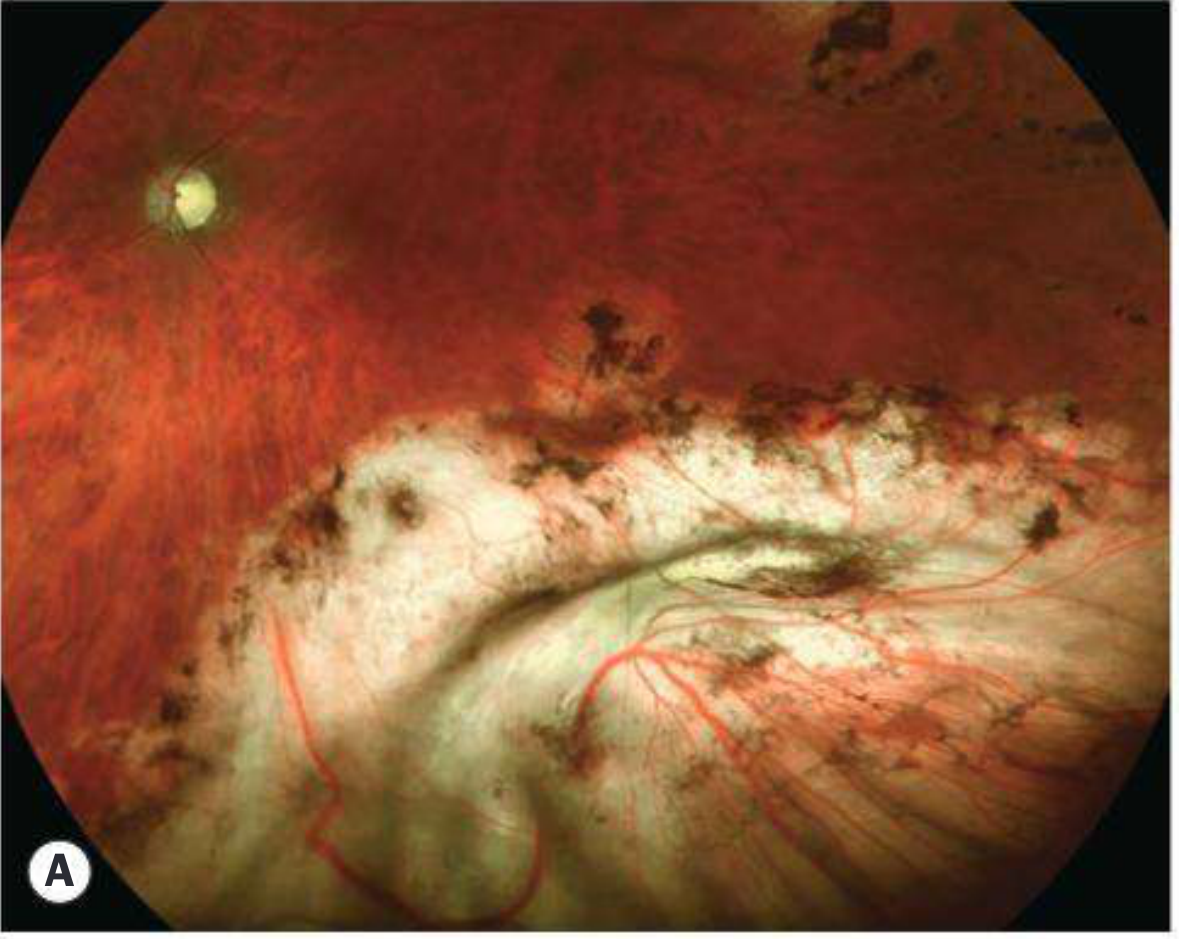

• Buckle extrusion — implant erodes through conjunctiva and becomes exposed (Fig. 16.32A — shows visible buckle material under conjunctiva)

Buckle extrusion — implant visible beneath conjunctiva

Fig. 16.32A — Buckle extrusion beneath conjunctiva

Plomb extrusion — silicone implant extruding through conjunctiva

Fig. 16.32B — Plomb (solid silicone) extrusion